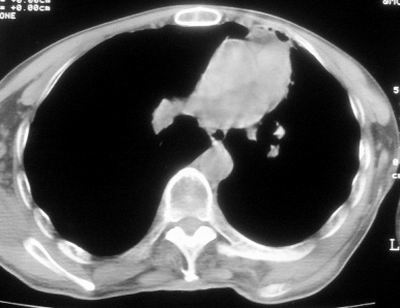

标题: CT11864:男,47岁,反复咳嗽、咯痰、咯血3年,请分析. [打印本页]

患者,男,47岁,反复咳嗽、咯痰、咯血3年,再发5天。痰培养未找到真菌、抗酸杆菌、癌细胞。

左肺上叶体积明显缩小,其内见多发透光区,纵隔向左侧移位,左肺下叶多发班片状病灶,边界模糊,1左肺上叶先天肺发育不全,2左肺下叶肺炎,

左肺上叶结核伴肺纤维化,纵隔移位,左肺下叶感染性病变,建议抗炎抗结核后复查,双肺气肿.

以下是引用xulianj在2008-2-25 21:01:00的发言:[br]左肺上叶结核伴肺纤维化有霉菌球形成,纵隔移位,左肺下叶感染性病变,建议抗炎抗结核后复查,双肺气肿.

考虑:左肺慢纤伴霉菌球形成、双肺全小叶型肺气肿。

1)考虑为:左肺上叶肺结核(空洞形成),伴左下肺感染;不排除霉菌感染可能。2)肺气肿。

左肺上叶结核伴肺纤维化空洞形成并左肺下叶感染,纵隔牵拉移位,建议作进一步检查排除左侧肺霉菌感染可能。